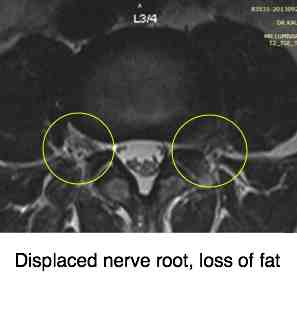

Displaced fat in the foramen points to a large disc prolapse.